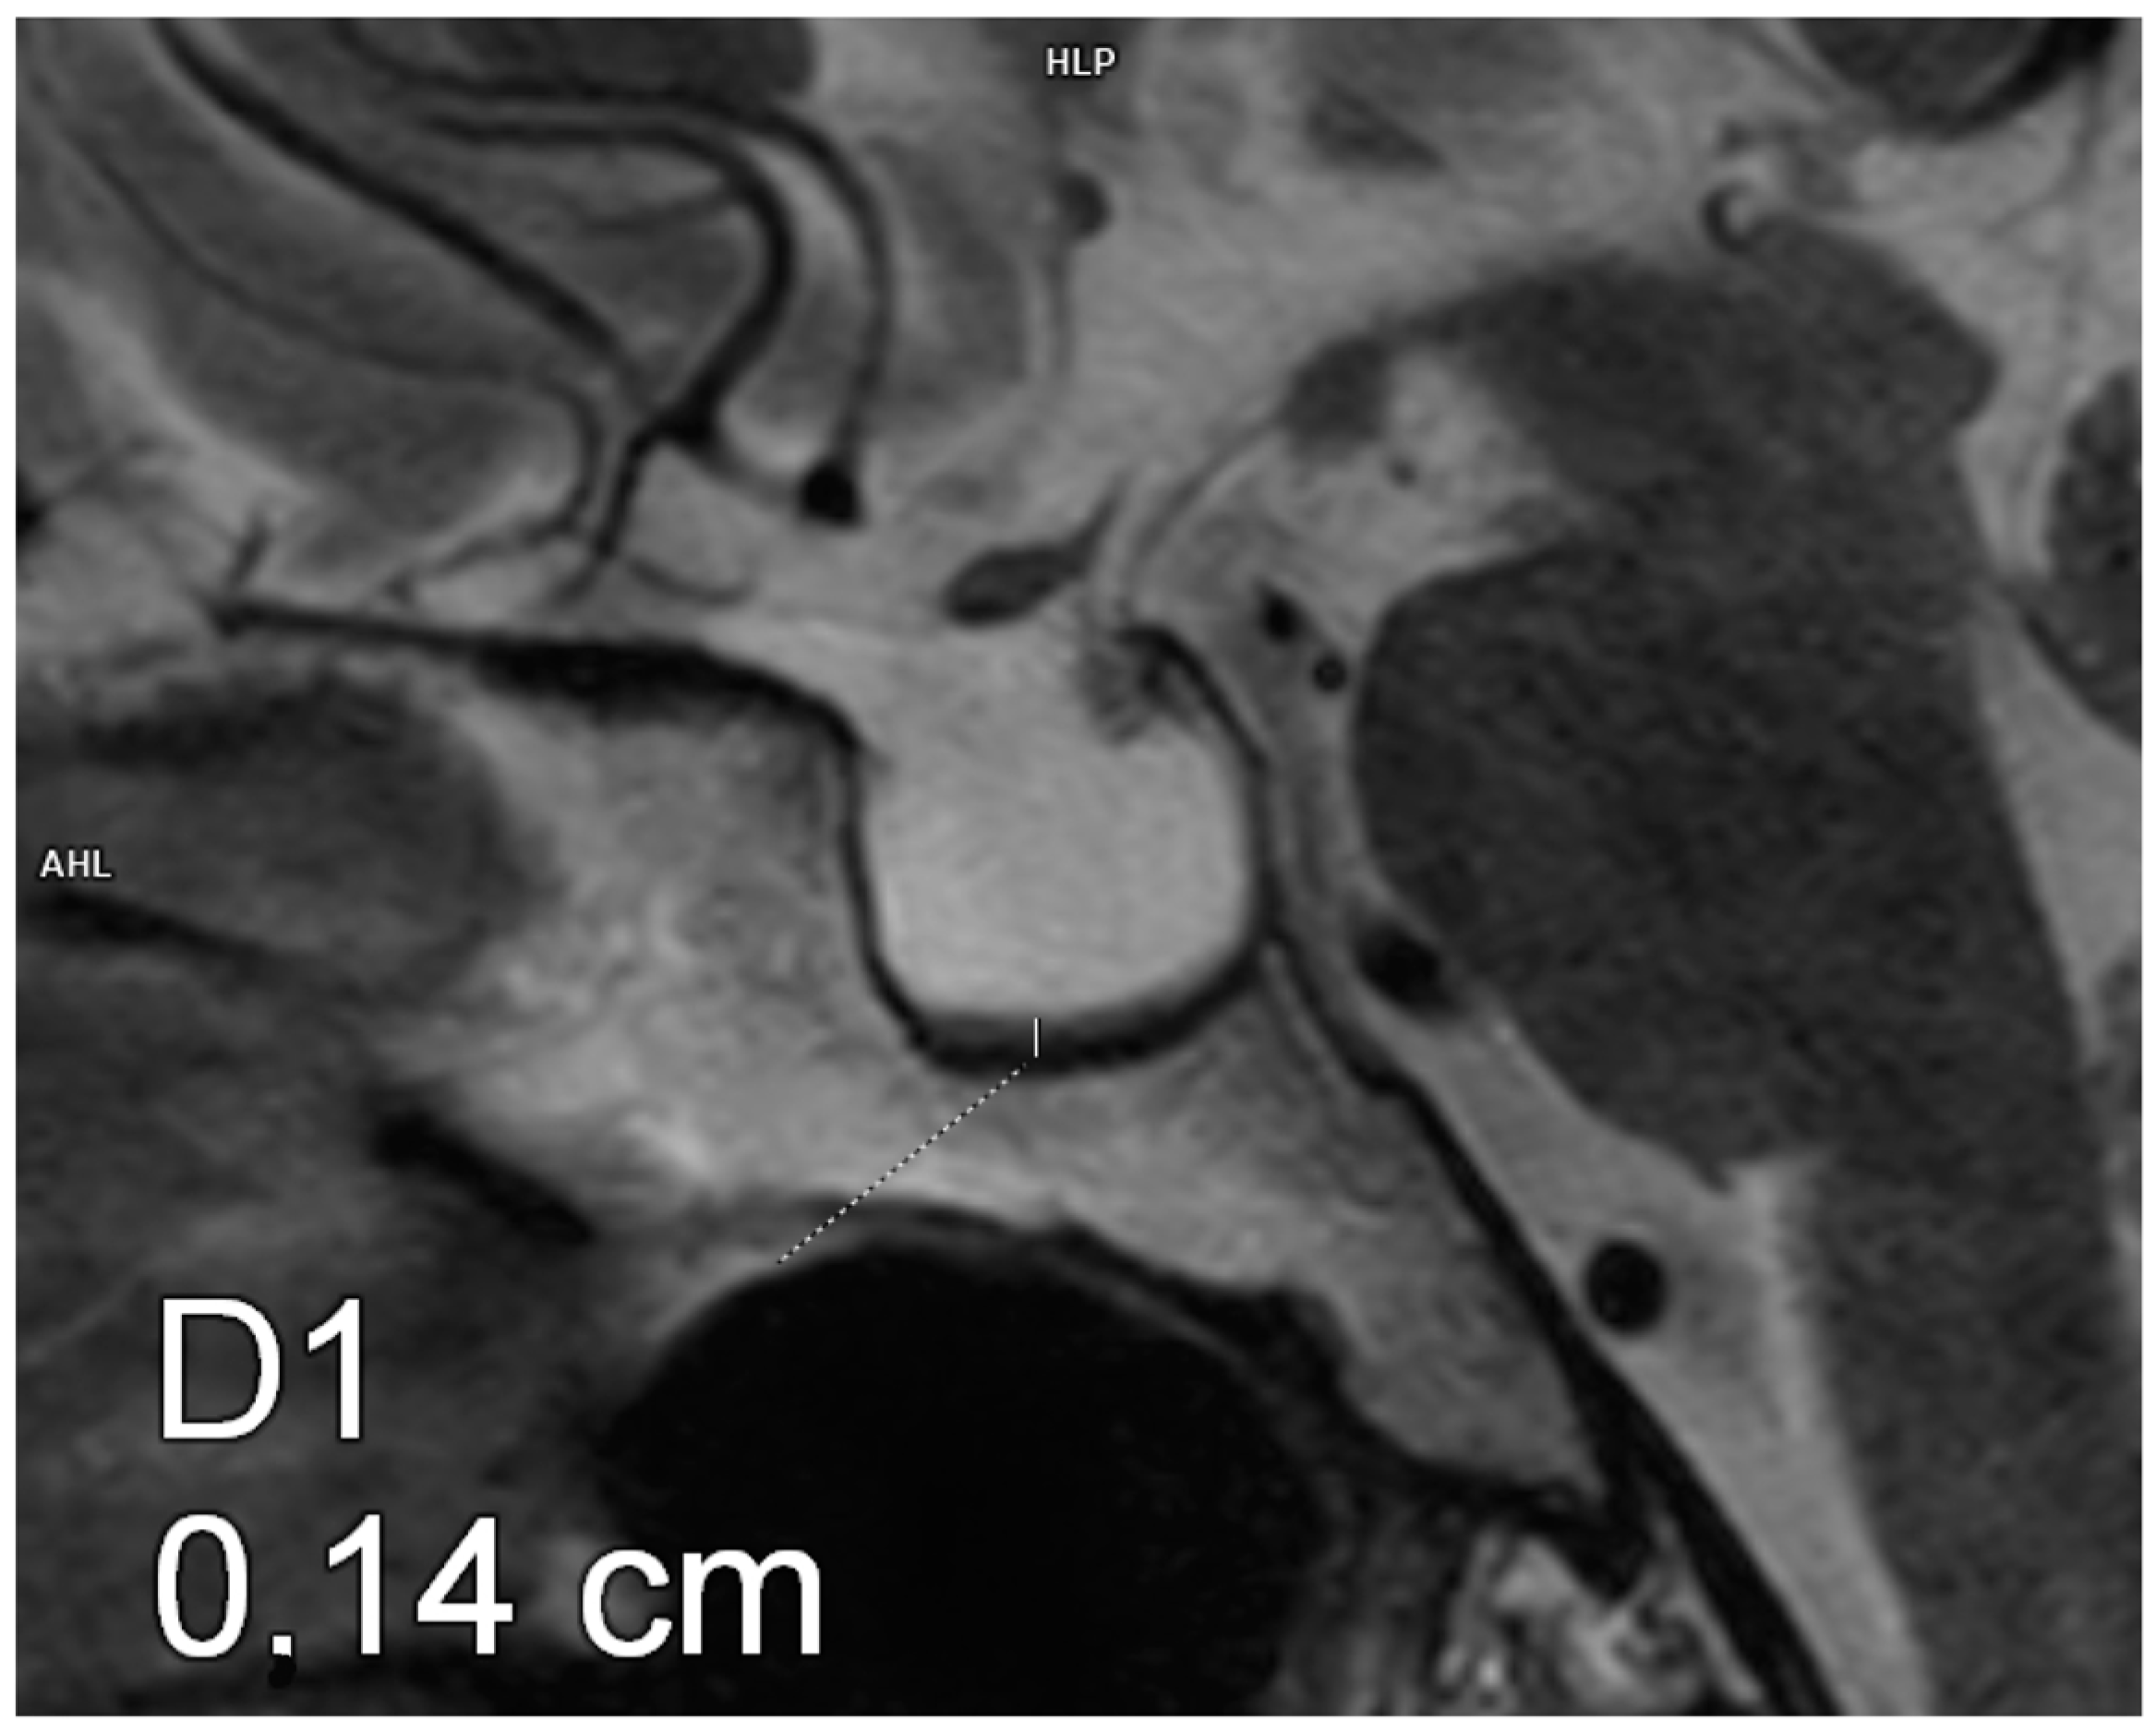

Figure 1.

Empty sella. Magnetic resonance imaging, T2-weighted image, sagittal plane. The craniocaudal diameter of the pituitary gland is 1.4 mm.